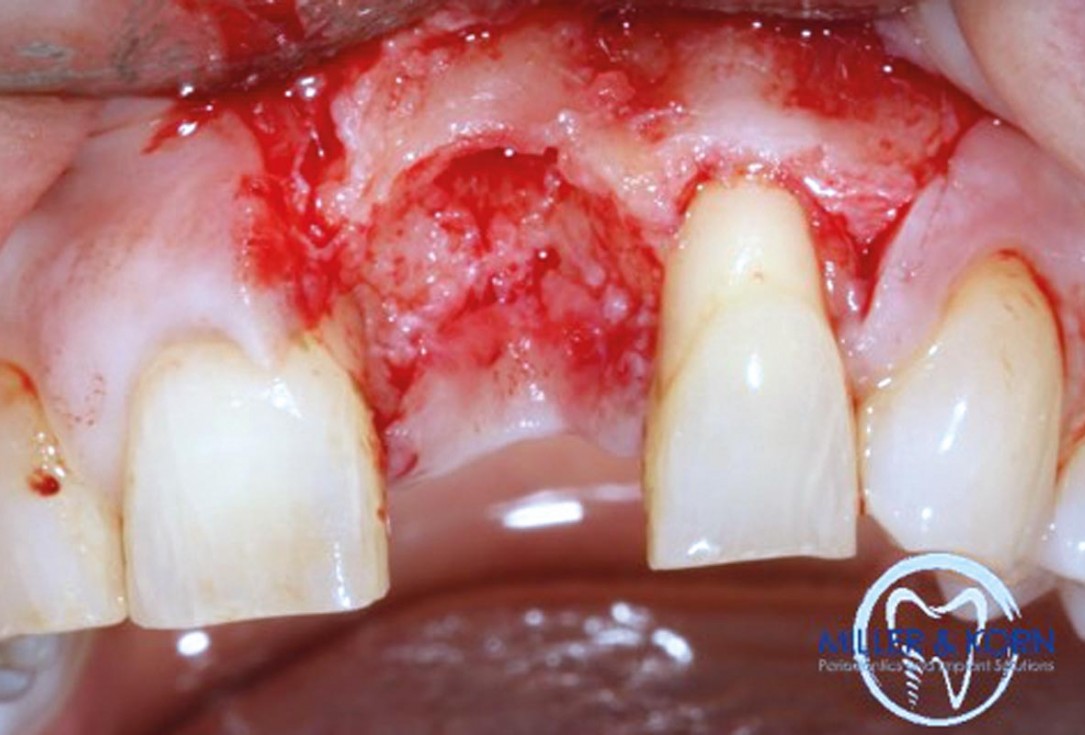

04/39 - Preparation of a full thickness flap and careful debridementImmediate implant placement and correction of horizontal and vertical bone loss using an allograft bone ring, cerabone® and Jason® membrane - Drs. Miller and Korn